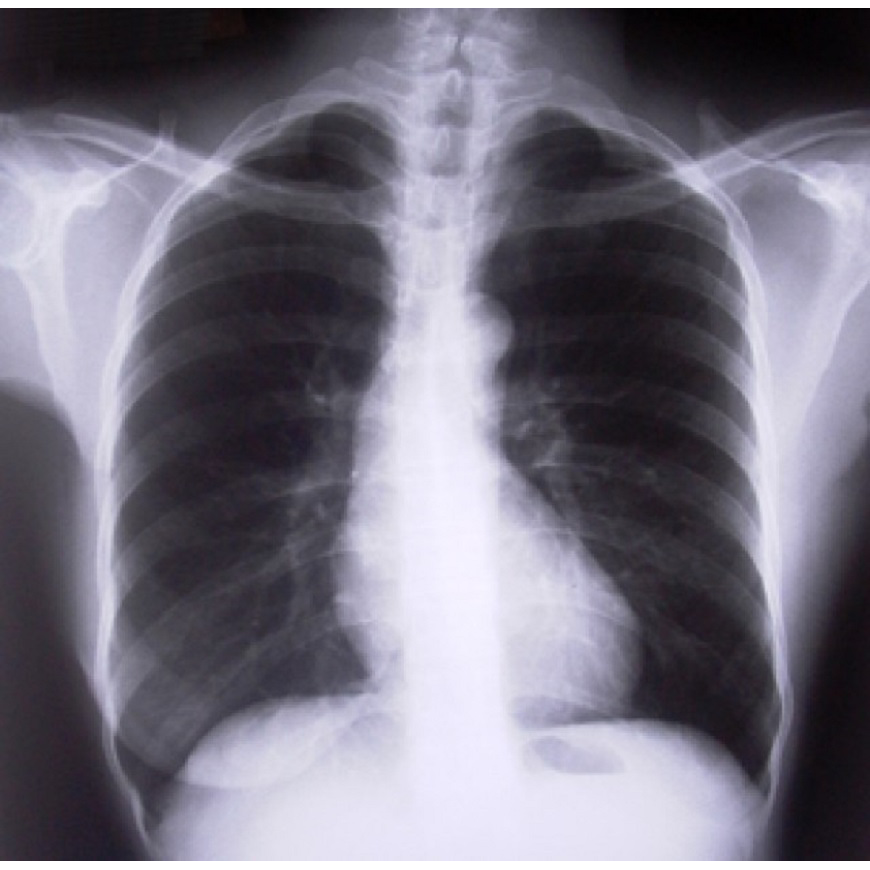

El diagnóstico para determinar si tienes EPOC se basa en los síntomas, un examen físico y los resultados de las pruebas de diagnóstico. La Espirometría es una prueba no invasiva para evaluar la función pulmonar. Durante la prueba, se respira profundamente y luego se sopla por un tubo conectado al espirómetro. También se cuenta con pruebas por imágenes que incluyen una radiografía de tórax o una tomografía computarizada. Las imágenes pueden proporcionar una vista detallada de los pulmones, vasos sanguíneos y corazón. Estas pruebas contribuirán además a detectar alguna otra afección diferente como asma, una enfermedad pulmonar restrictiva o insuficiencia cardíaca.